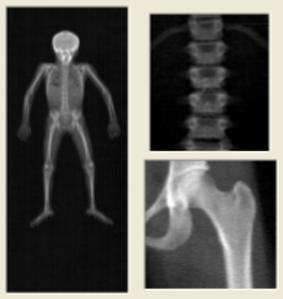

Dit zijn röntgenfoto’s

Na een tijd word je naar de onderzoekskamer gebracht. In deze kamer staat het röntgentoestel en een bed. Hier moet je tijdens het maken van de foto’s op liggen. Het röntgentoestel gaat twee of drie foto’s van je botten maken: een van je rug, een van je heup en soms ook een van je hele lichaam. Om de foto van je rug goed te kunnen maken, krijg je een kussen onder je benen en voor de foto van je heup moet je je tenen naar elkaar toe draaien. Tijdens het maken van de foto’s mag je niet bewegen. Tussen de opnamen door mag je wel bewegen.